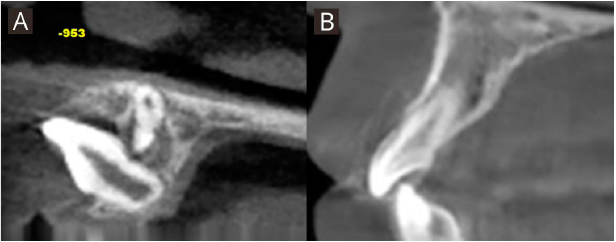

Paciente de género femenino de 9 años de edad, sin antecedentes mórbidos, perfil convexo, clase II esqueletal. En el análisis intraoral se observó dentición mixta primera fase, ausencia del diente 21, neutroclusión molar bilateral, discrepancia óseo-dentoalveolar moderada superior y severa inferior, relación transversal favorable, línea media dentaria superior desviada un milímetro a la izquierda respecto a la línea facial y la línea media dentaria inferior centrada con la línea media facial (Figura 1. A-D). En el análisis con CBCT, realizado con el software Nemotec® se observó el diente 21 en evolución intraósea en una posición alta, horizontal y paralelo al plano oclusal, con formación radicular incompleta, con una distancia de 26.39 milímetros al borde incisal del incisivo central contralateral, y asociado a este se encontró un diente supernumerario en posición alta en relación con el piso de fosas nasales, de forma coronaria cónica ubicado hacia palatino (Figura 2. A-B). En la primera fase de tratamiento, se inició por la desinclusión del diente supernumerario y luego se abordó el diente 21 mediante una exposición quirúrgica cerrada realizada por un cirujano maxilofacial, en el mismo acto quirúrgico se instaló un botón vestibular y uno palatino de refuerzo con ligadura de acero inoxidable de 0.9 Ferderhard (FH) para la tracción. Se realizó instalación de biteblock céntrico, el cual consistió en un dispositivo interoclusal cementado confeccionado en articulador digital para mantener la funcionalidad masticatoria y evitar contactos prematuros, y que tiene un botón central para otorgar rigidez que fue activado ¼ de vuelta a diario por 12 días. Desde este botón se confeccionó un brazo de tracción en alambre de acero inoxidable de calibre 0.8 FH, realizando la activación de la tracción 15 días posterior a la cirugía cada cuatro semanas, dejando la encía del reborde marginal levemente isquémica con una fuerza de aproximadamente 50 gramos (Medidor de tensión VTSYIQI model ATG-500-2 ®) (Figura 3. A-B).

Figura 2 Representación tridimensional de posición inicial de diente 21 evaluado en CBCT. A. Vista frontal. B. Vista axial.